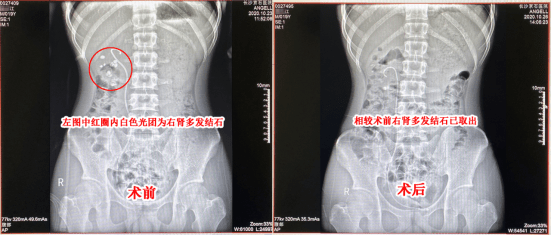

肾结石不疼可以不管吗?正确做法是啥?俗话说,“千里之堤,溃于蚁穴”。 对于我们的身体而言,这“蚁穴”可能就是一些平时不被在意的小病小痛,比如——肾结石。 每年体检季,总有... 大于20毫米的结石:属于“危险玩家”,必须通过手术方式清除,以免引发更严重的并发症。 得了肾结石,怎么正确预防和治疗? 多喝水,让尿液流动...